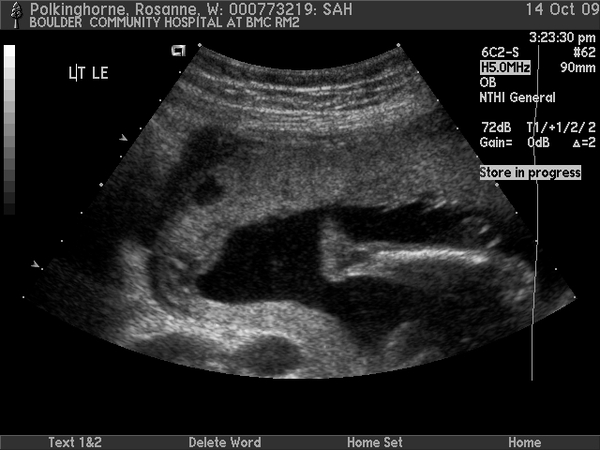

Sam in utero